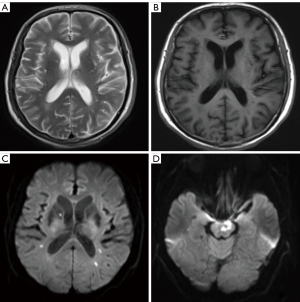

A 72-year-old male patient was admitted to the hospital due to nausea and vomiting, which had developed nausea and vomiting 8 days ago, leading to an acute onset of the disease. He had a history of hepatitis C for more than 10 years and diabetes for more than 20 years. After admission, abdominal contrast-enhanced computed tomography (CT) showed the S4 segment of the left lobe of the liver had a round-like nodule with rich blood supply. It was enhanced by “fast in and fast out”, suggestive of primary hepatocellular carcinoma (Figure 1), and head magnetic resonance imaging (MRI) indicated multiple acute cerebral infarctions in both cerebral hemispheres and the brain stem (Figure 2). Magnetic resonance angiography (MRA) of cerebral vessels showed no obvious stenosis of intracranial vessels. He was then transferred to the department of neurology for further treatment. Special physical examination revealed the following: clear, mild dysarthria, shallow right nasolabial groove, showing left deviation of tooth and mouth angle, right upper limb muscle strength of 4 levels, other limb muscle strength of 5 levels, and positive bilateral pathological signs. The results of hemogram were as follows: D-dimer 8,800.00 ng/mL, fibrinogen 1.52 g/L, thrombin time 19.70 seconds, hepatitis C antibody 68.92 IU/L. After admission, an electrocardiogram (ECG) showed a sinus heart rate. A small amount of mitral regurgitation was detected by echocardiography, and the left ventricular systolic function was normal. Heparin, circulation improvement, and neurotrophic and symptomatic support treatment were given to the patient; his cough symptoms improved, and his walking and speech were steady and clear. After 15 days, another head MRI was performed, and it was found that the high signal intensity of diffusion-weighted imaging (DWI) in bilateral cerebral hemispheres had disappeared, and the high signal range of brain stem DWI had decreased (Figure 3). After anticoagulant therapy, another coagulogram was performed, which revealed the following: D-dimer 187.00 ng/mL, fibrinogen 3.04 g/L, thrombin time 16.50 seconds. At 20 days after the patient’s condition had become stable, the liver tumor was treated by laparoscopic ultrasound-guided radiofrequency ablation. A post-surgical coagulogram revealed the following: D-dimer 1,081.00 ng/mL, fibrinogen 2.57 g/L, thrombin time 13.40 seconds. All procedures performed in this study were in accordance with the ethical standards of the institutional and/or national research committee(s) and with the Helsinki Declaration (as revised in 2013). Written informed consent was obtained from the patient for publication of this article and accompanying images. A copy of the written consent is available for review by the editorial office of this journal.

On MRI, Trousseau’s syndrome-related strokes usually involve more than 2 regions of the brain, often with bilateral anterior and posterior circulation, which is known as the triple-zone sign, and is a helpful clue for diagnosing Trousseau’s syndrome (14). In the case reported herein, the patient had multiple acute cerebral infarctions in both cerebral hemispheres and brainstem, which is consistent with the manifestation of the triple zone sign. A study reported that frequency of the triple zone sign in Trousseau’s syndrome was 6 times higher than that of atrial fibrillation-associated cerebral infarction, and its sensitivity and specificity were 23.4% and 96.4%, respectively (15).